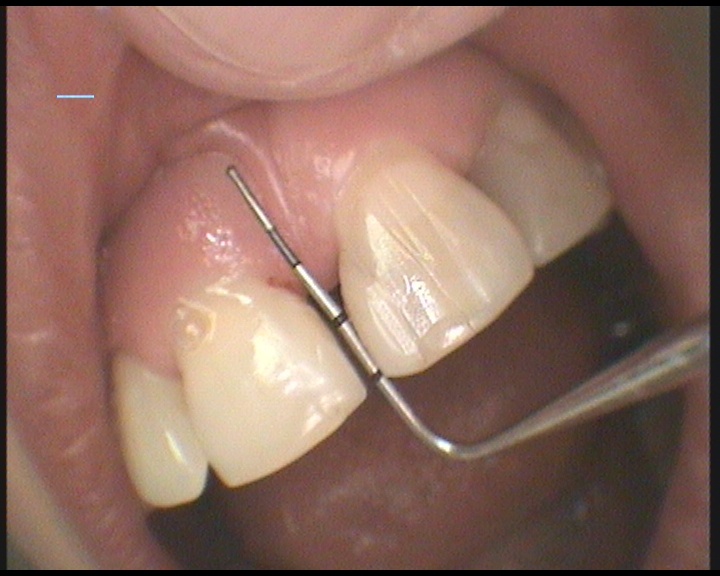

V našem stomatologickém centru se využívá pro ošetření kořenových kanálků operační mikroskop a příslušné mikroskopické techniky. Důvodem, proč používáme operační mikroskop je fakt, že dřeňová dutina, ze které vystupují kořenové kanálky bývá obvykle malá, málo přehledná a těžko ji lze běžným ordinačním světlem dostatečně osvětlit. Operační mikroskop umožňuje mnohonásobné zvětšení dřeňové dutiny i vstupy do jednotlivých kanálků. Lékař pak vidí konkrétní detail o velikosti asi jako kopací míč. Práce je pak mnohem přesnější a detailnější.

Operační mikroskop navíc přes svoji optiku svítí do dřeňové dutiny silným LED světlem, což je pro přesnost a kvalitu práce velmi důležité. Tím dosahujeme při ošetření kořenových kanálků velmi dobré a hlavně dlouhodobé úspěšnosti . Navíc nám to umožňuje ošetřovat i zuby s komplikovaným kořenovým systémem , které jsou v běžné ordinaci bez mikroskopu prakticky neošetřitelné a musí se extrahovat (vytrhnout).